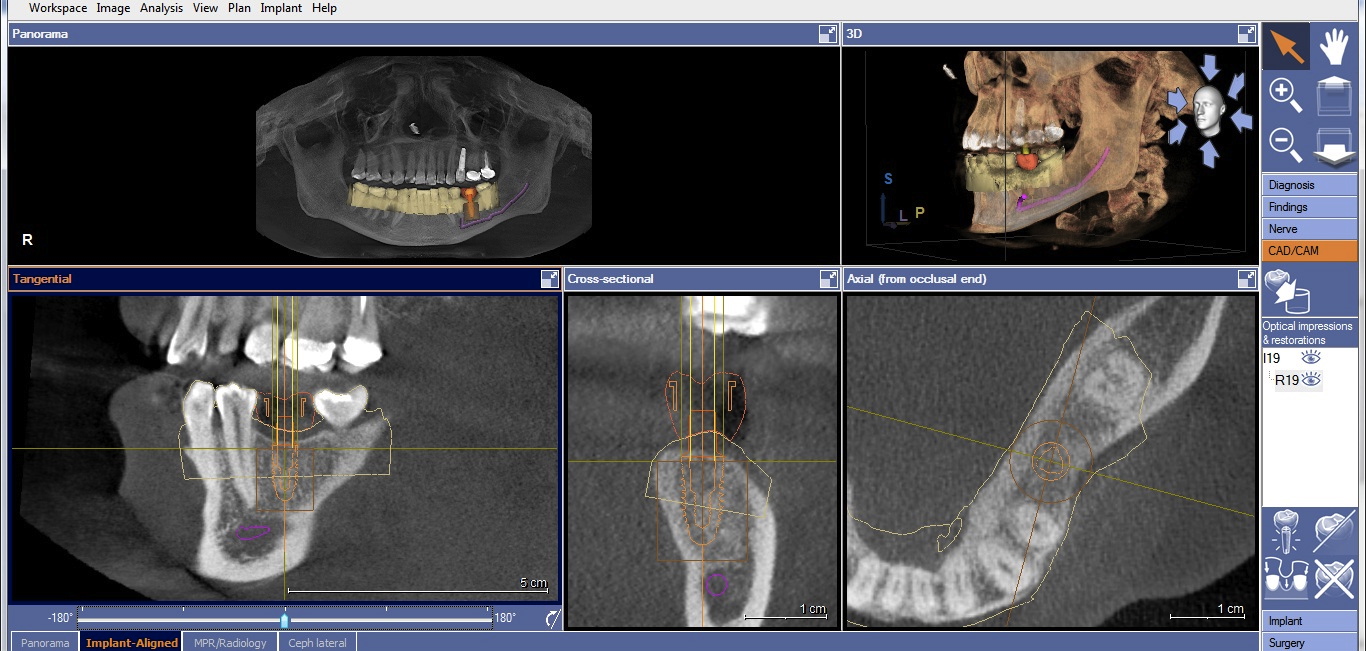

Once the desired restorative outcome is in a digital format, the patient’s CBCT scan is opened in the implant-planning software. If the edentulous space is in the posterior mandible, the inferior alveolar nerve bundle (IANB) is traced so that it is highlighted and avoided by the planned implant (Figure 2). Now, the patient’s digital restoration can be imported. Once imported, most software requires the user to identify corresponding landmarks on the digitized model and on the CBCT to merge the two data sets. It is best to avoid using teeth with crowns or large restorations as landmarks, because they cause distortions in CBCT scans and may result in inaccuracies in data set merges. Once complete, merge accuracy is verified by the user and is either confirmed or reset.

Two factors affect implant depth: distance to the proximal contact and surrounding the implant with 1 mm of bone. The implant platform should be 5 mm or less from the proximal contact for proper papilla formation.21,22 Accounting for prosthetic components, the distance to the occlusal surface should be approximately 7 mm (5 mm abutment + 2 mm ceramic). If placing the restorative platform at the osseous crest does not provide this space, it is necessary to remove bone so the implant can be submerged to proper depth. However, if placing the platform 7 mm from the restorative surface does not result in surrounding the implant with 1 mm of bone, a decision must be made. The deficiency will usually be on the facial. The practitioner must either submerge the implant until there is sufficient bone surrounding it, or if this places the implant too deeply, augment the ridge prior to implant placement. Current guided regeneration techniques can predictably gain up to 5.5 mm horizontally23 and 10 mm to 12 mm vertically.24 Once the implant platform is set, the final apical length of the implant can be adjusted and the digital plan is complete (Figure 3).

CBCT with final implant plan. Note the digital restoration, TiBase abutment, and highlighted IANB.

Figure 3